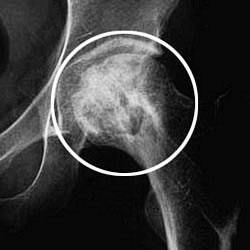

大腿骨頚部骨折 画像診断シリーズ10 鹿児島市の脳神経外科 ひらやま脳神経外科